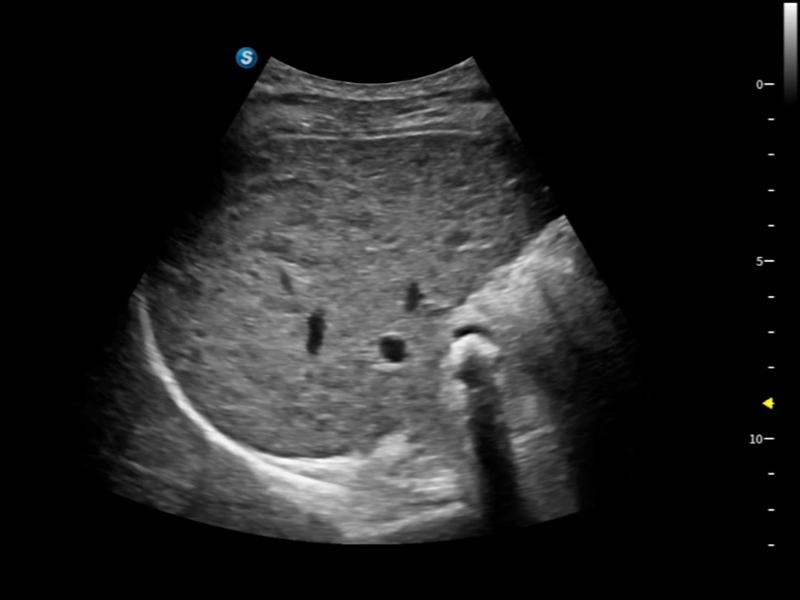

豐富的血流動(dòng)力學(xué)檢測(cè)技術(shù),可在不同醫(yī)療場(chǎng)景中高效捕捉血流信號(hào),助力臨床診療。

在傳統(tǒng)血流的基礎(chǔ)上優(yōu)化掃查和算法策略,能夠更好的抑制組織信息,提煉紅細(xì)胞運(yùn)動(dòng)信息,得到更高幀頻,高靈敏度和分辨率的血流信號(hào),還原更真實(shí)的血流動(dòng)力學(xué)。